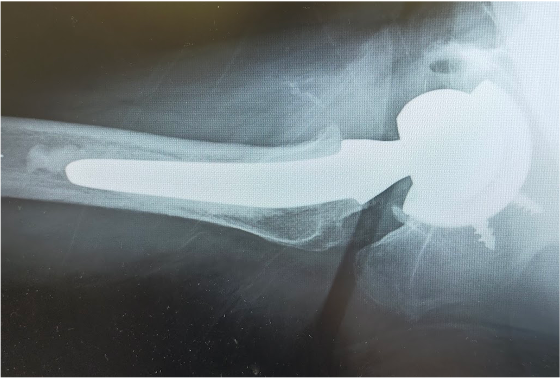

〈手術後のレントゲン〉(側面)